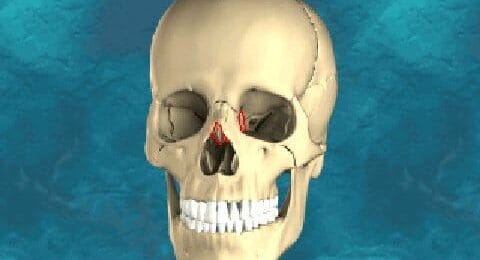

Zeefbeen

De zeefbeendelen (pars os ethmoideus) bevinden zich tus...

Traanbeen

De traanbeentjes zijn twee van de kleinste botjes in he...